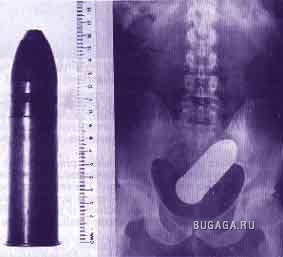

Ни для кого теперь уже не секрет, что у людей есть жопы. У каждого она своя и у всех разные. Жопы бывают человеческие и другие, большие и маленькие, плоские и выпуклые, висячие и упругие, в общем, всякие. А еще жопы бывают сытые и голодные. У кого сытая попа, тот её холит и лелеет, она вся такая ранимая и нежная. А у кого голодная жопа, тот её пичкает всем, что попадётся под руку, может затолкать туда всё, что угодно. Такую жопу ничто не берёт. Ни слово, ни дело, ни заноза, ни пуля, ни штык, ни добрый подсрачник! Прозвали их люди чудо-жопы! Чудо-жопы имеет не каждый, а только тот, кто регулярно упражняется в скармливании жопе различных инородных предметов. Этих ректальных сластолюбцев люди тоже кое-как прозвали, но мы не будем отвлекаться, с нас достаточно знать факт, что люди имеют жопы. Кто воспламенел желанием поэкспериментировать, но не знает, что именно засунуть в недра своего драгоценного проголодавшегося зверя, предлагаю посмотреть варианты. Ну а кому просто интересно, тот глазеет на серию снимков, сделанных медиками в разное время и в разных странах, но в одинаково патологичных случаях. Можно также прочитать пару случаев кормления, и чем это закончилось. Кого картинки могут задеть за живое, не принимайте близко к… живому :):):)

Вибраторы -23

Фалоимитаторы -15